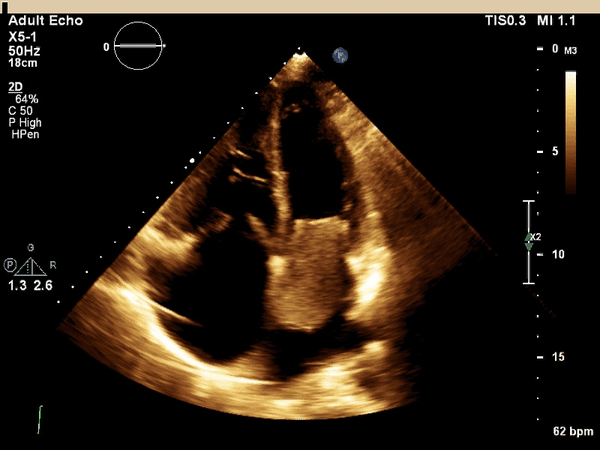

The above echo images demonstrate several abnormalities.

There is moderate systolic dysfunction (EF 36%),

There is a large left atrial mass measuring 5.5 x 3 cm,

The mass is obstructing mitral inflow and causing moderate mitral regurgitation,

There is severe tricuspid regurgitation and right atrial dilation

confirmed by the absence of coaption of the tricuspid leaflets and

systolic flow reversal in the inferior vena cava.